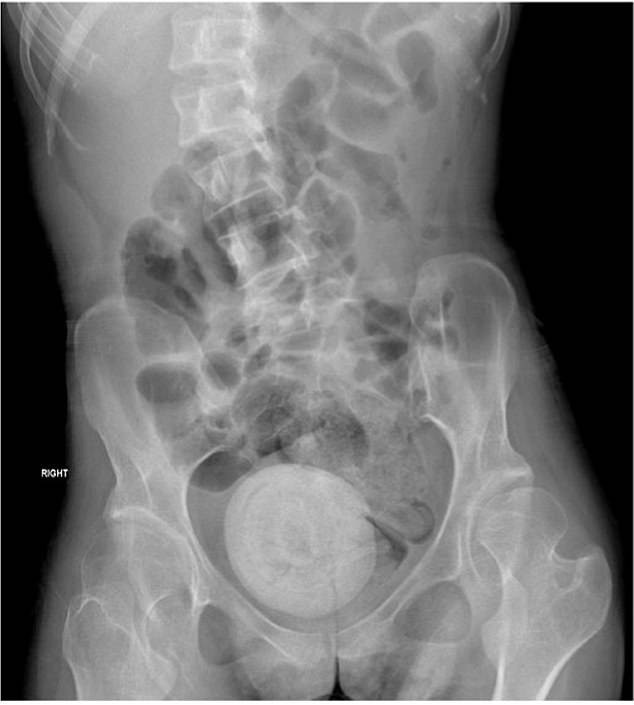

Hình ảnh chụp CT cho thấy viên sỏi âm đạo to bằng quả cam nằm ở vùng chậu của người phụ nữ. Ảnh: Dailymail

Các bác sĩ cho biết cô trông xanh xao và lờ đờ. Họ tiến hành chụp CT  trên bụng và xương chậu của cô ấy, và hình ảnh cho thấy một khối tròn, lớn ở vùng xương chậu.